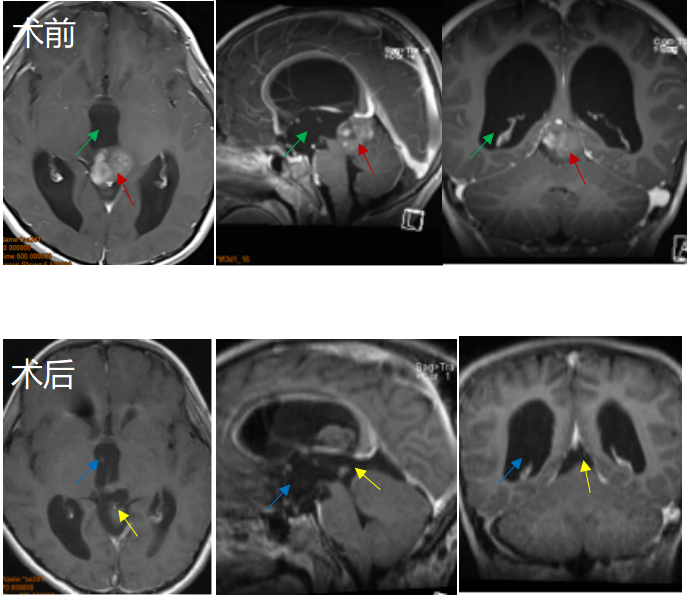

8岁男孩因头痛、眼球运动障碍等症状,检查结果为“松果体区占位合并幕上梗阻性脑积水”,一家人问遍了国内各地专家,得到的答复多是建议做脑脊液分流加辅助放化疗。事实证明,这些手段对控制小A的病情发展作用并不大。后远程咨询INC巴特朗菲教授,教授表示有手术指征,可以全切。于是带其前往教授所在的德国INI国际神经学研究中心进行手术,手术过程中,患者俯卧位,后正中头皮切口,取幕下枕下乙状窦旁小脑上入路结合幕上经小脑幕入路,较终肿瘤得以全切除,且尽力减少了组织的损伤,对预防后期肿瘤的复发起到了较大作用。

术后一天小A依然保持清醒状态,在术后ICU观察两天之后情况良好,无明显并发症且顺利出院。目前,小A之前的各种症状全都消失,恢复了正常机体功能,较近复查时肿瘤也并无增长。